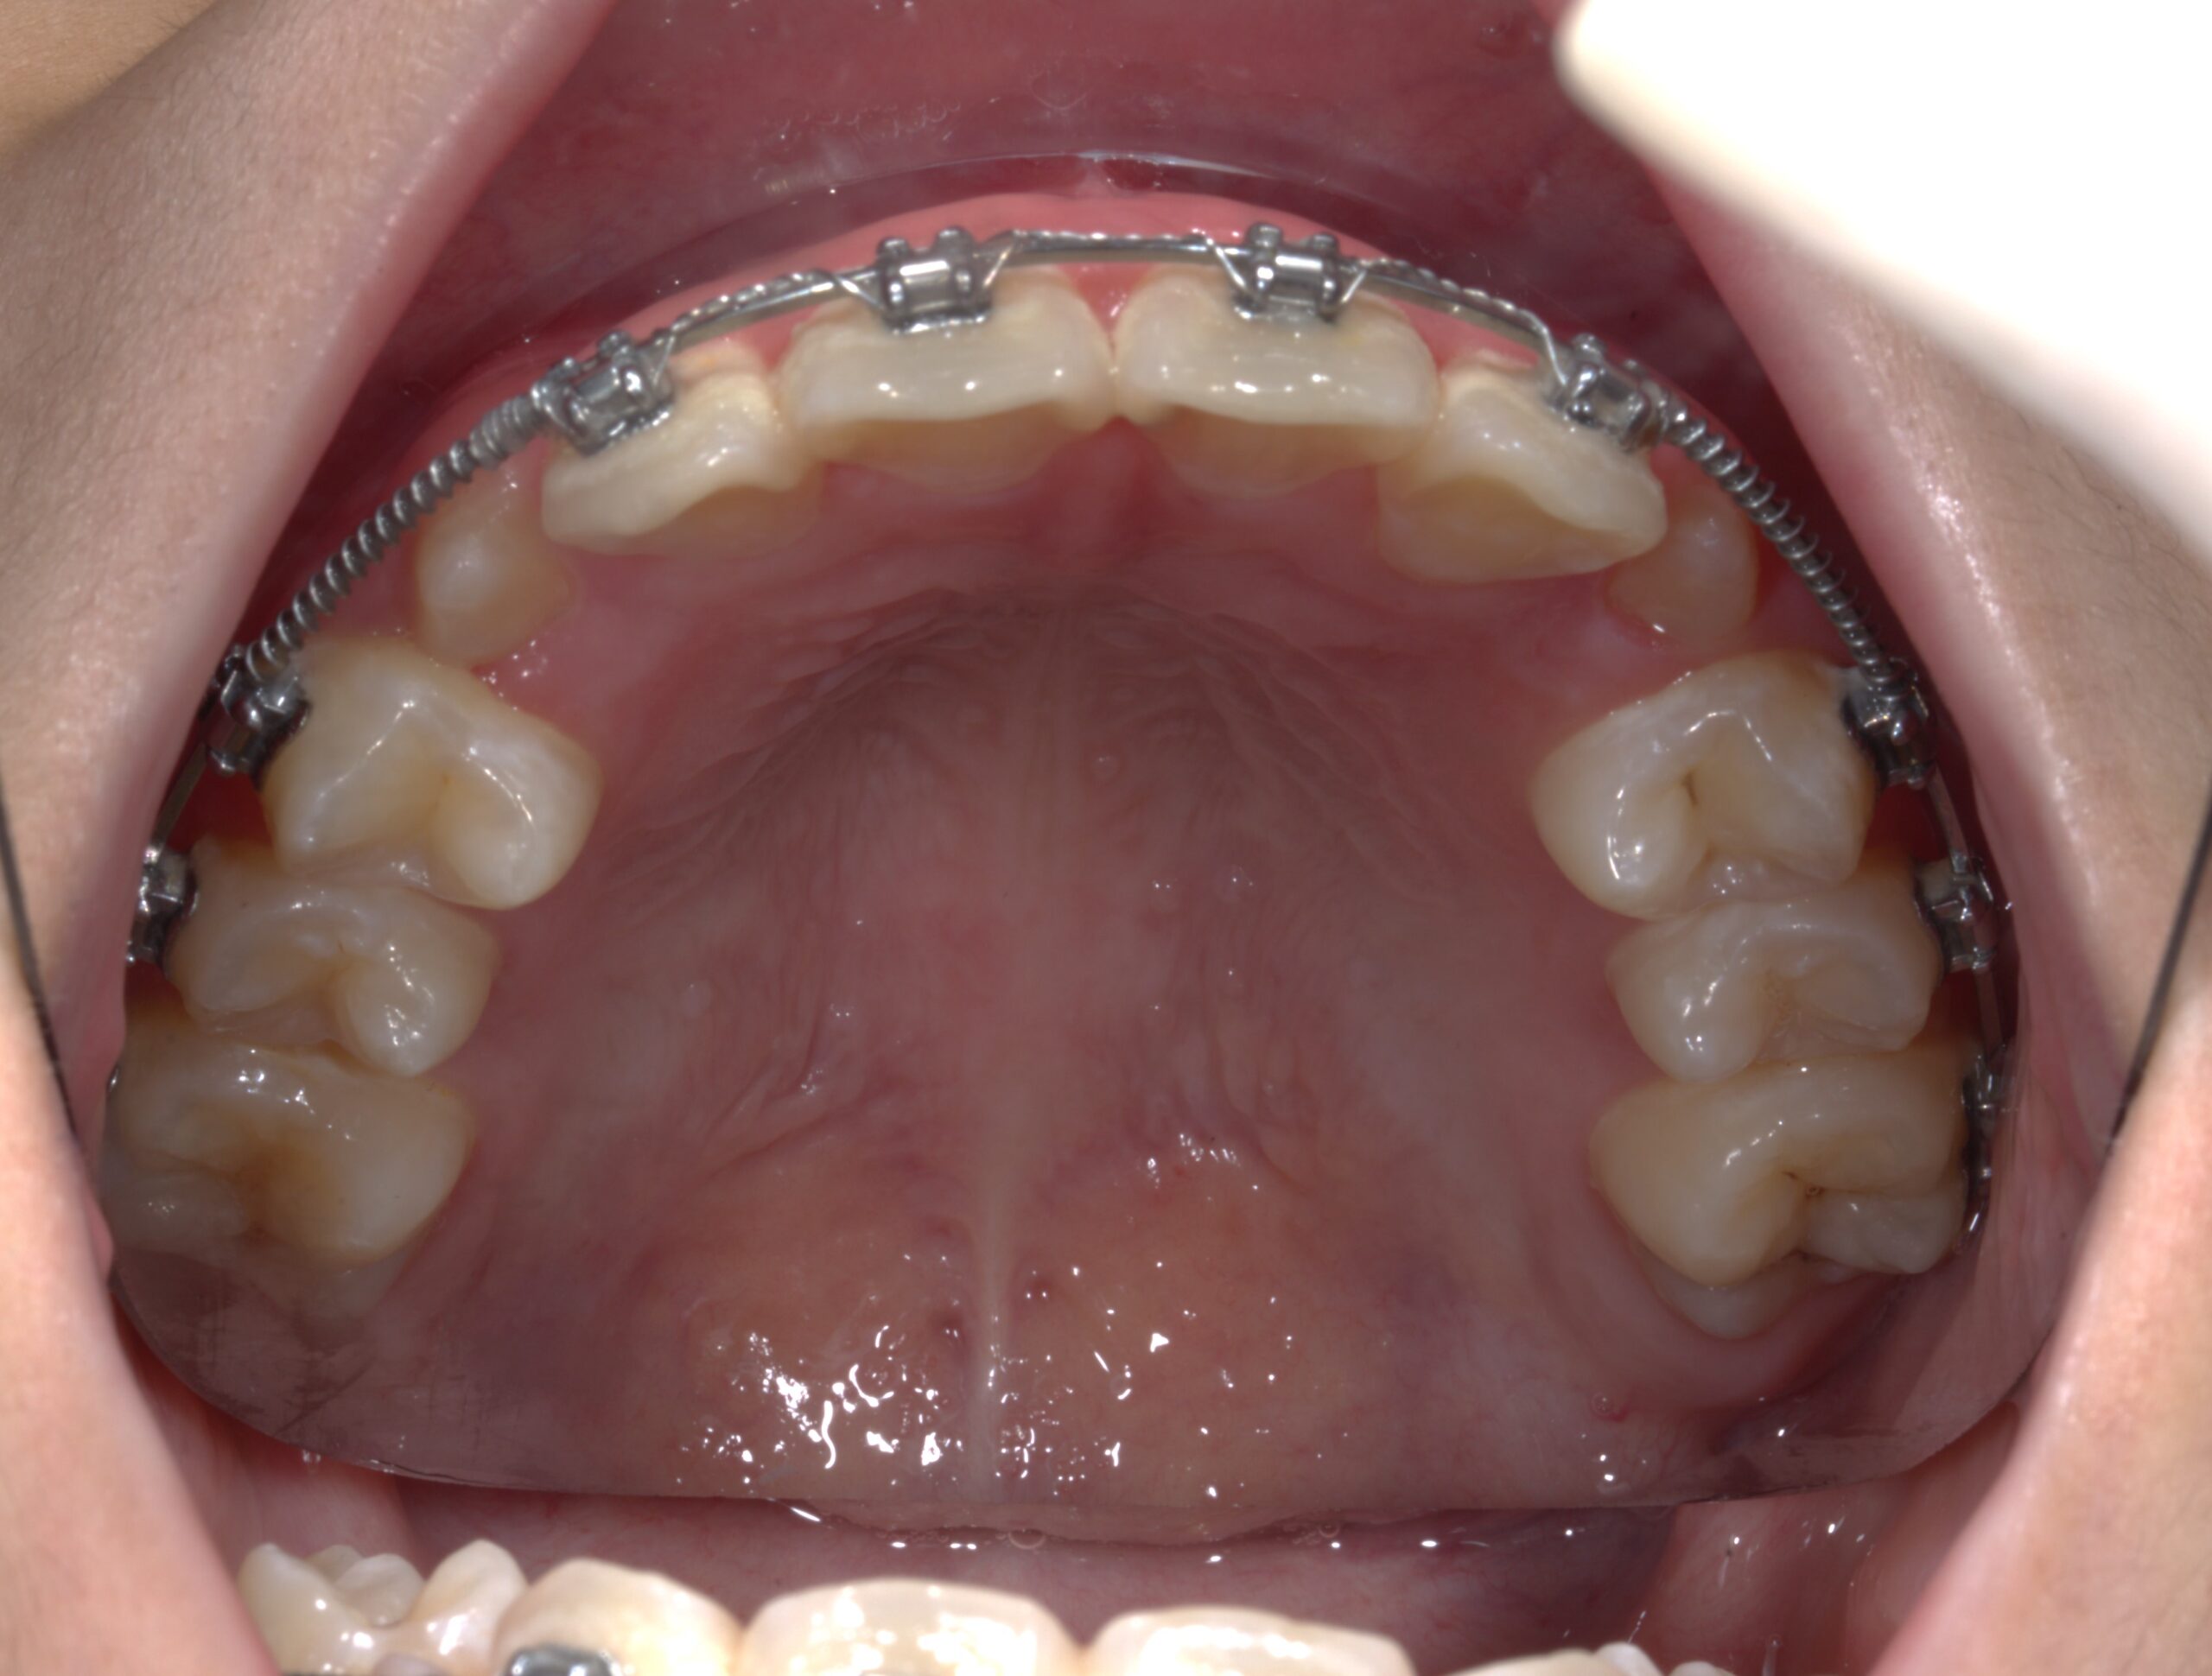

Niềng răng (hay chỉnh nha) là phương pháp sử dụng khí cụ nha khoa (như mắc cài kim loại, sứ hoặc khay trong suốt) để dịch chuyển răng về đúng vị trí mong muốn. Đây là phương pháp điều trị các vấn đề như:

Niềng răng giúp cân chỉnh khớp cắn

Niềng răng giúp:

✅ Dịch chuyển răng về đúng vị trí

✅ Phân bố lực nhai đều

✅ Tạo khớp cắn chuẩn, phòng tránh các bệnh lý răng miệng lâu dài.